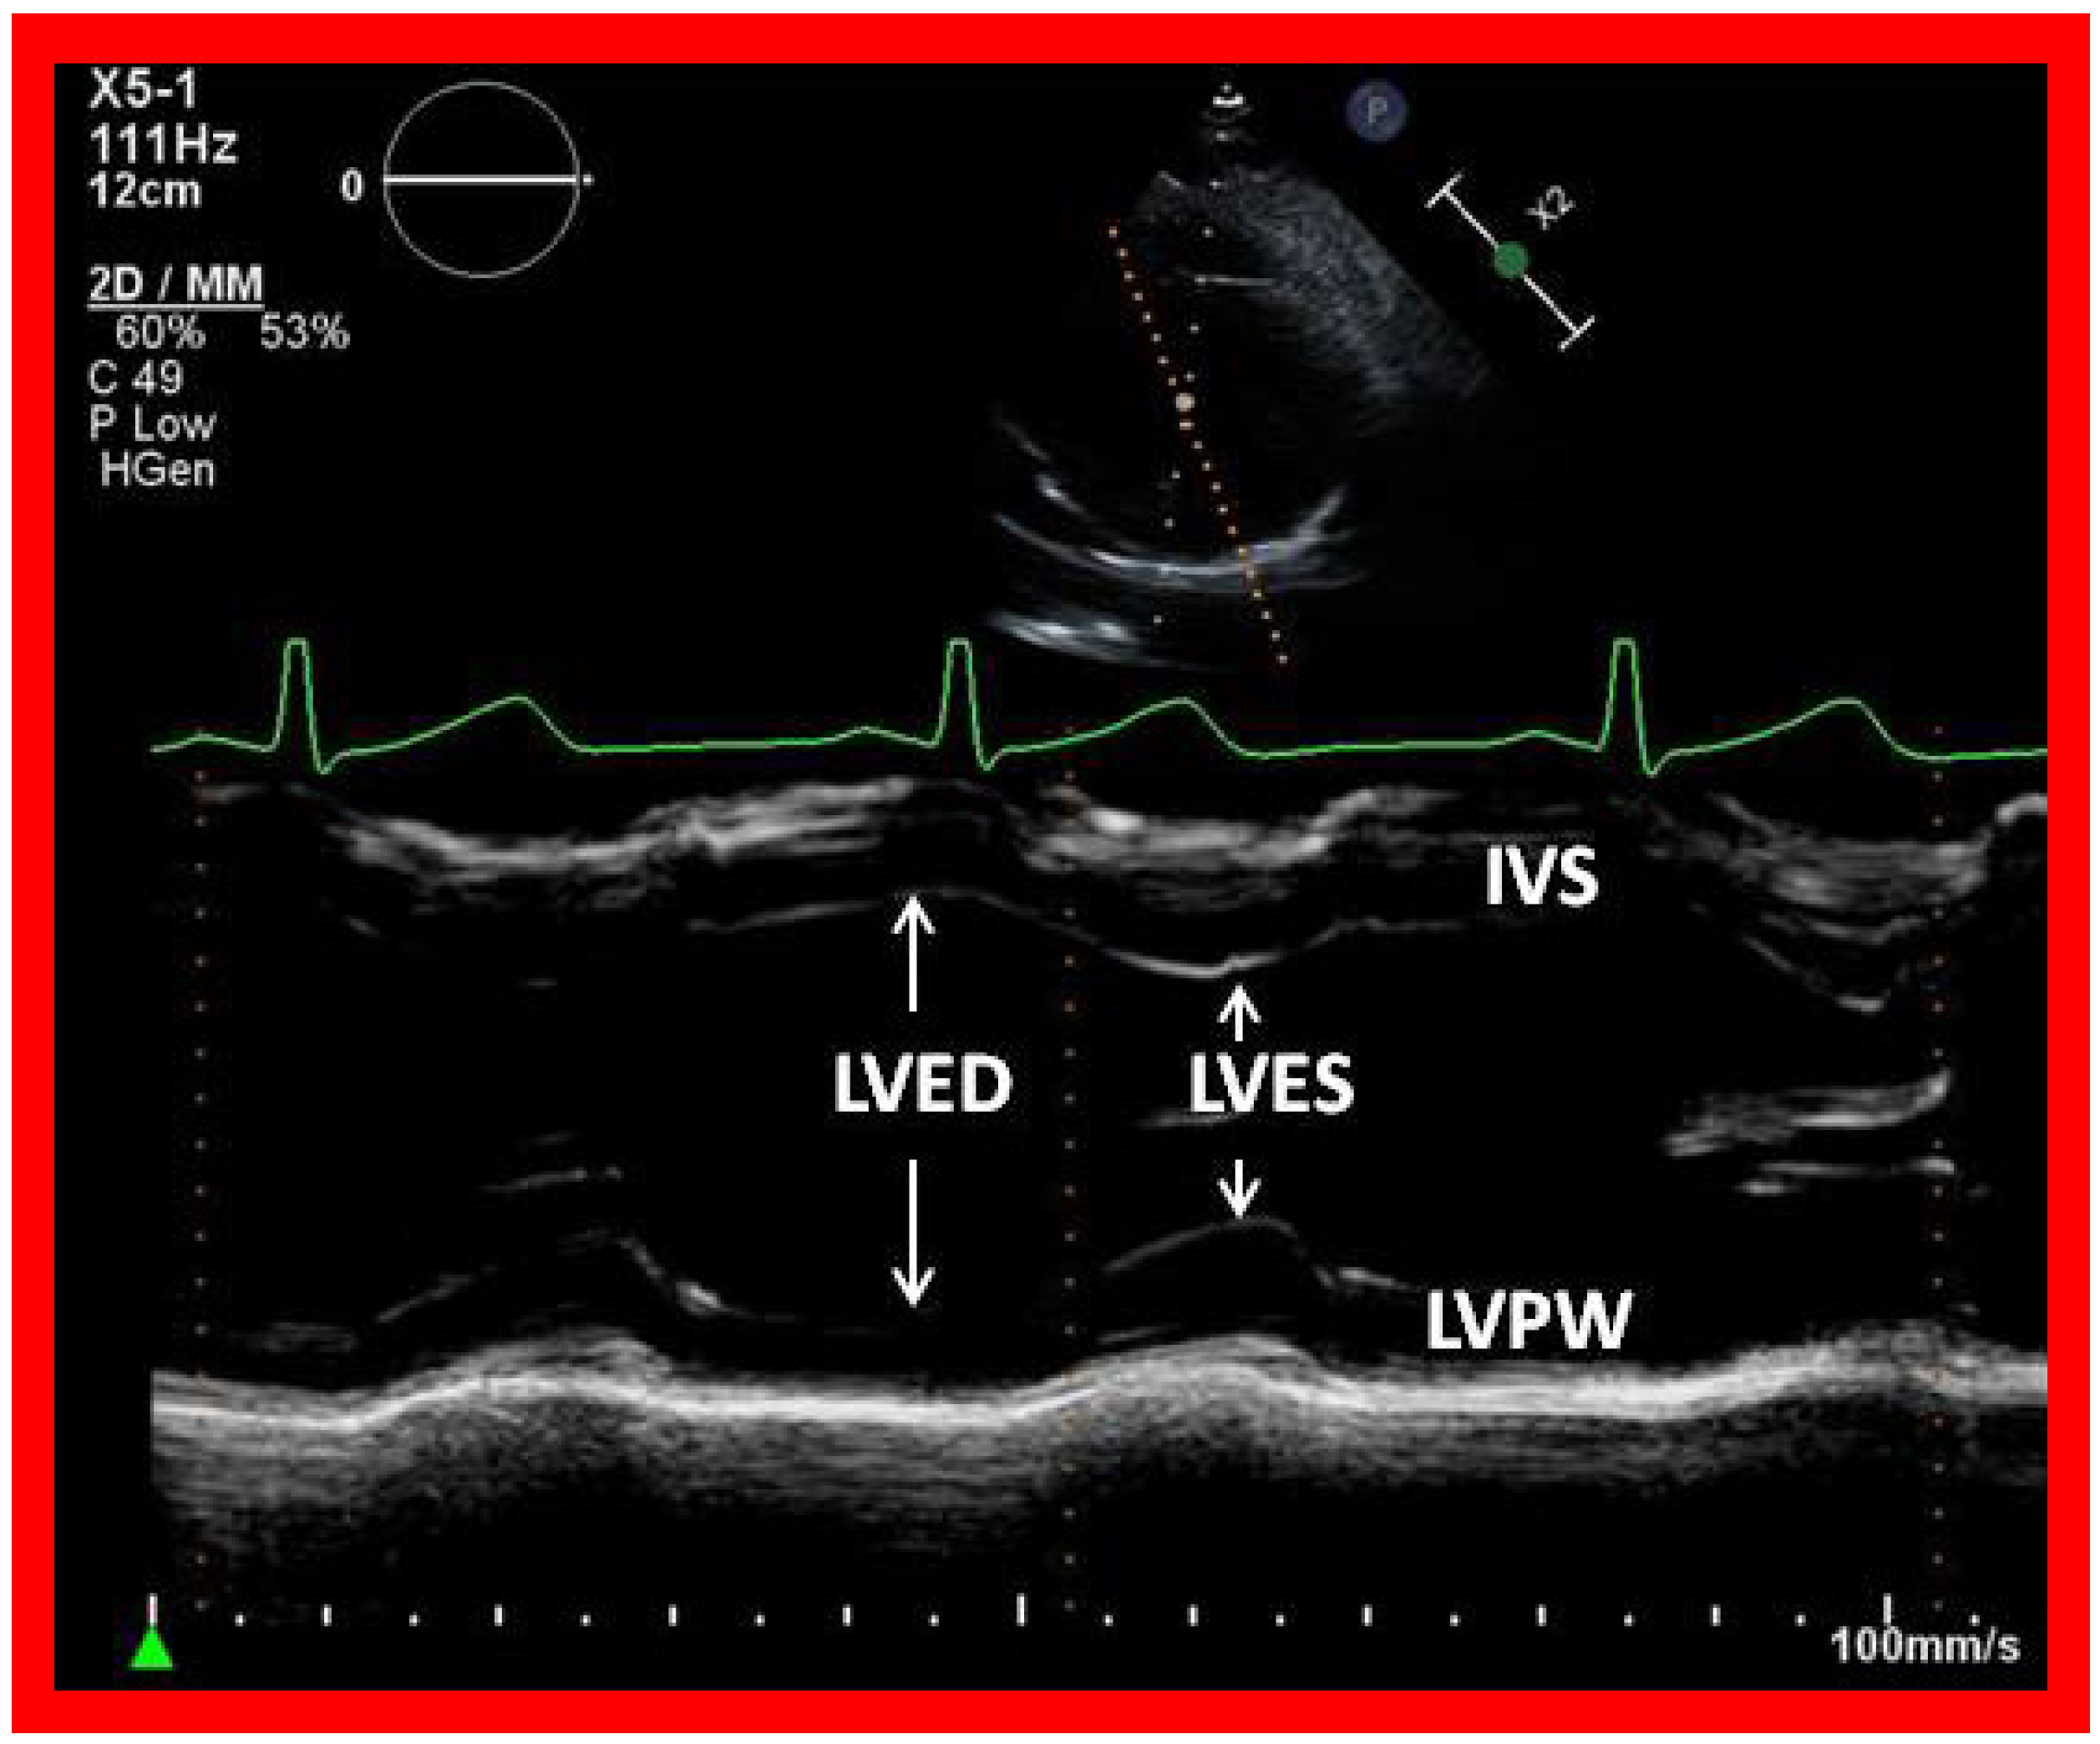

In most patients, LV size and function (Figure 17) remain within normal range, although large surgical shunts and inadequate PA banding may result in the deterioration of LV function. Consequently, periodic echo studies to monitor LV systolic function are recommended.

Figure 17. Selected video frame showing left ventricle in end diastole (LVED) and in end systole (LVES) demonstrating normal function. IVS, interventricular septum; LVPW, left ventricular posterior wall.